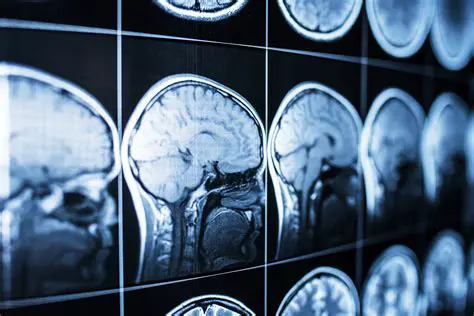

Choroby neurodegeneracyjne